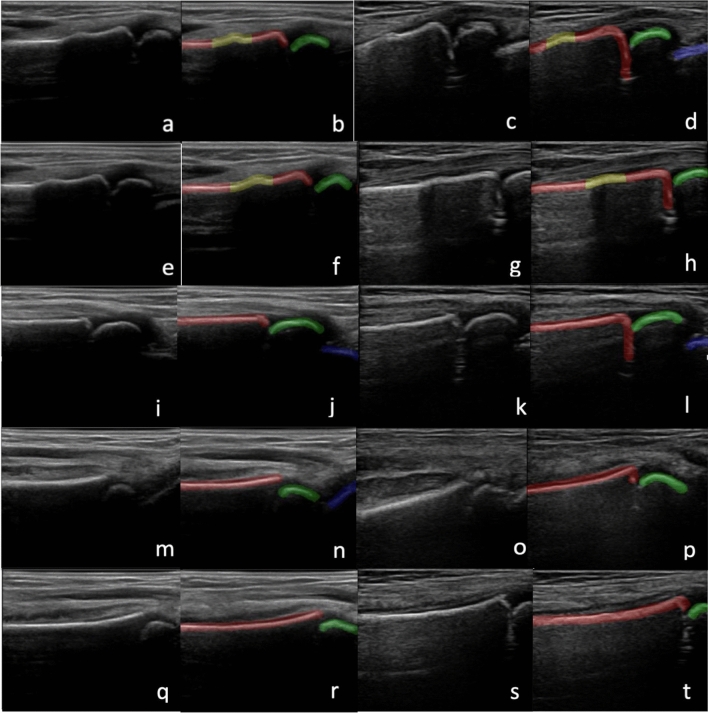

Images acquired with each machine included (1) the dorsal aspect of the distal radius with metaphysis, epiphysis, and first row of carpal bones visible, (2) a more proximal portion of the dorsal aspect of the distal radius with metaphysis and epiphysis visible, (3) the radial aspect of the distal radius with metaphysis, epiphysis, and first row of carpal bones visible, (4) the volar aspect of the distal radius with metaphysis, epiphysis, and first row of carpal bones visible and (5) a more proximal portion of the volar aspect of the distal radius with metaphysis and epiphysis visible (Fig. 1). Upon completion of this imaging protocol we were left with 5 3DUS sweeps and 5 2DUS sweeps for a total of 10 US sweeps for each symptomatic wrist.

Figure 1.

Images with corresponding manual labels of DRF including 3D dorsal (a,b), 2D dorsal (c,d), 3D proximal dorsal (e,f), 2D proximal dorsal (g,h), 3D radial (i,j) 2D radial (k,l), 3D volar (m,n), 2D volar (o,p), 3D proximal volar (q,r) and 2D proximal volar (s,t) views. Labels include radial metaphysis (red), epiphysis (green), carpal bones (blue) and fracture (yellow).

An experienced sonographer manually labeled each US image that was contained within the US sweeps (Fig. 1). Labeling was done using ITK-Snap (version 3.8.0) and included radial metaphysis (red), radial epiphysis (green), carpal bones (blue) and fractures (yellow). Images with a yellow label were categorized as positive for fracture, and those without a yellow label were categorized as negative. Individual fracture labels were compared with gold standard radiographs. Only individuals with the same label generated by manual segmentation and radiographs were used for AI model training and evaluation.